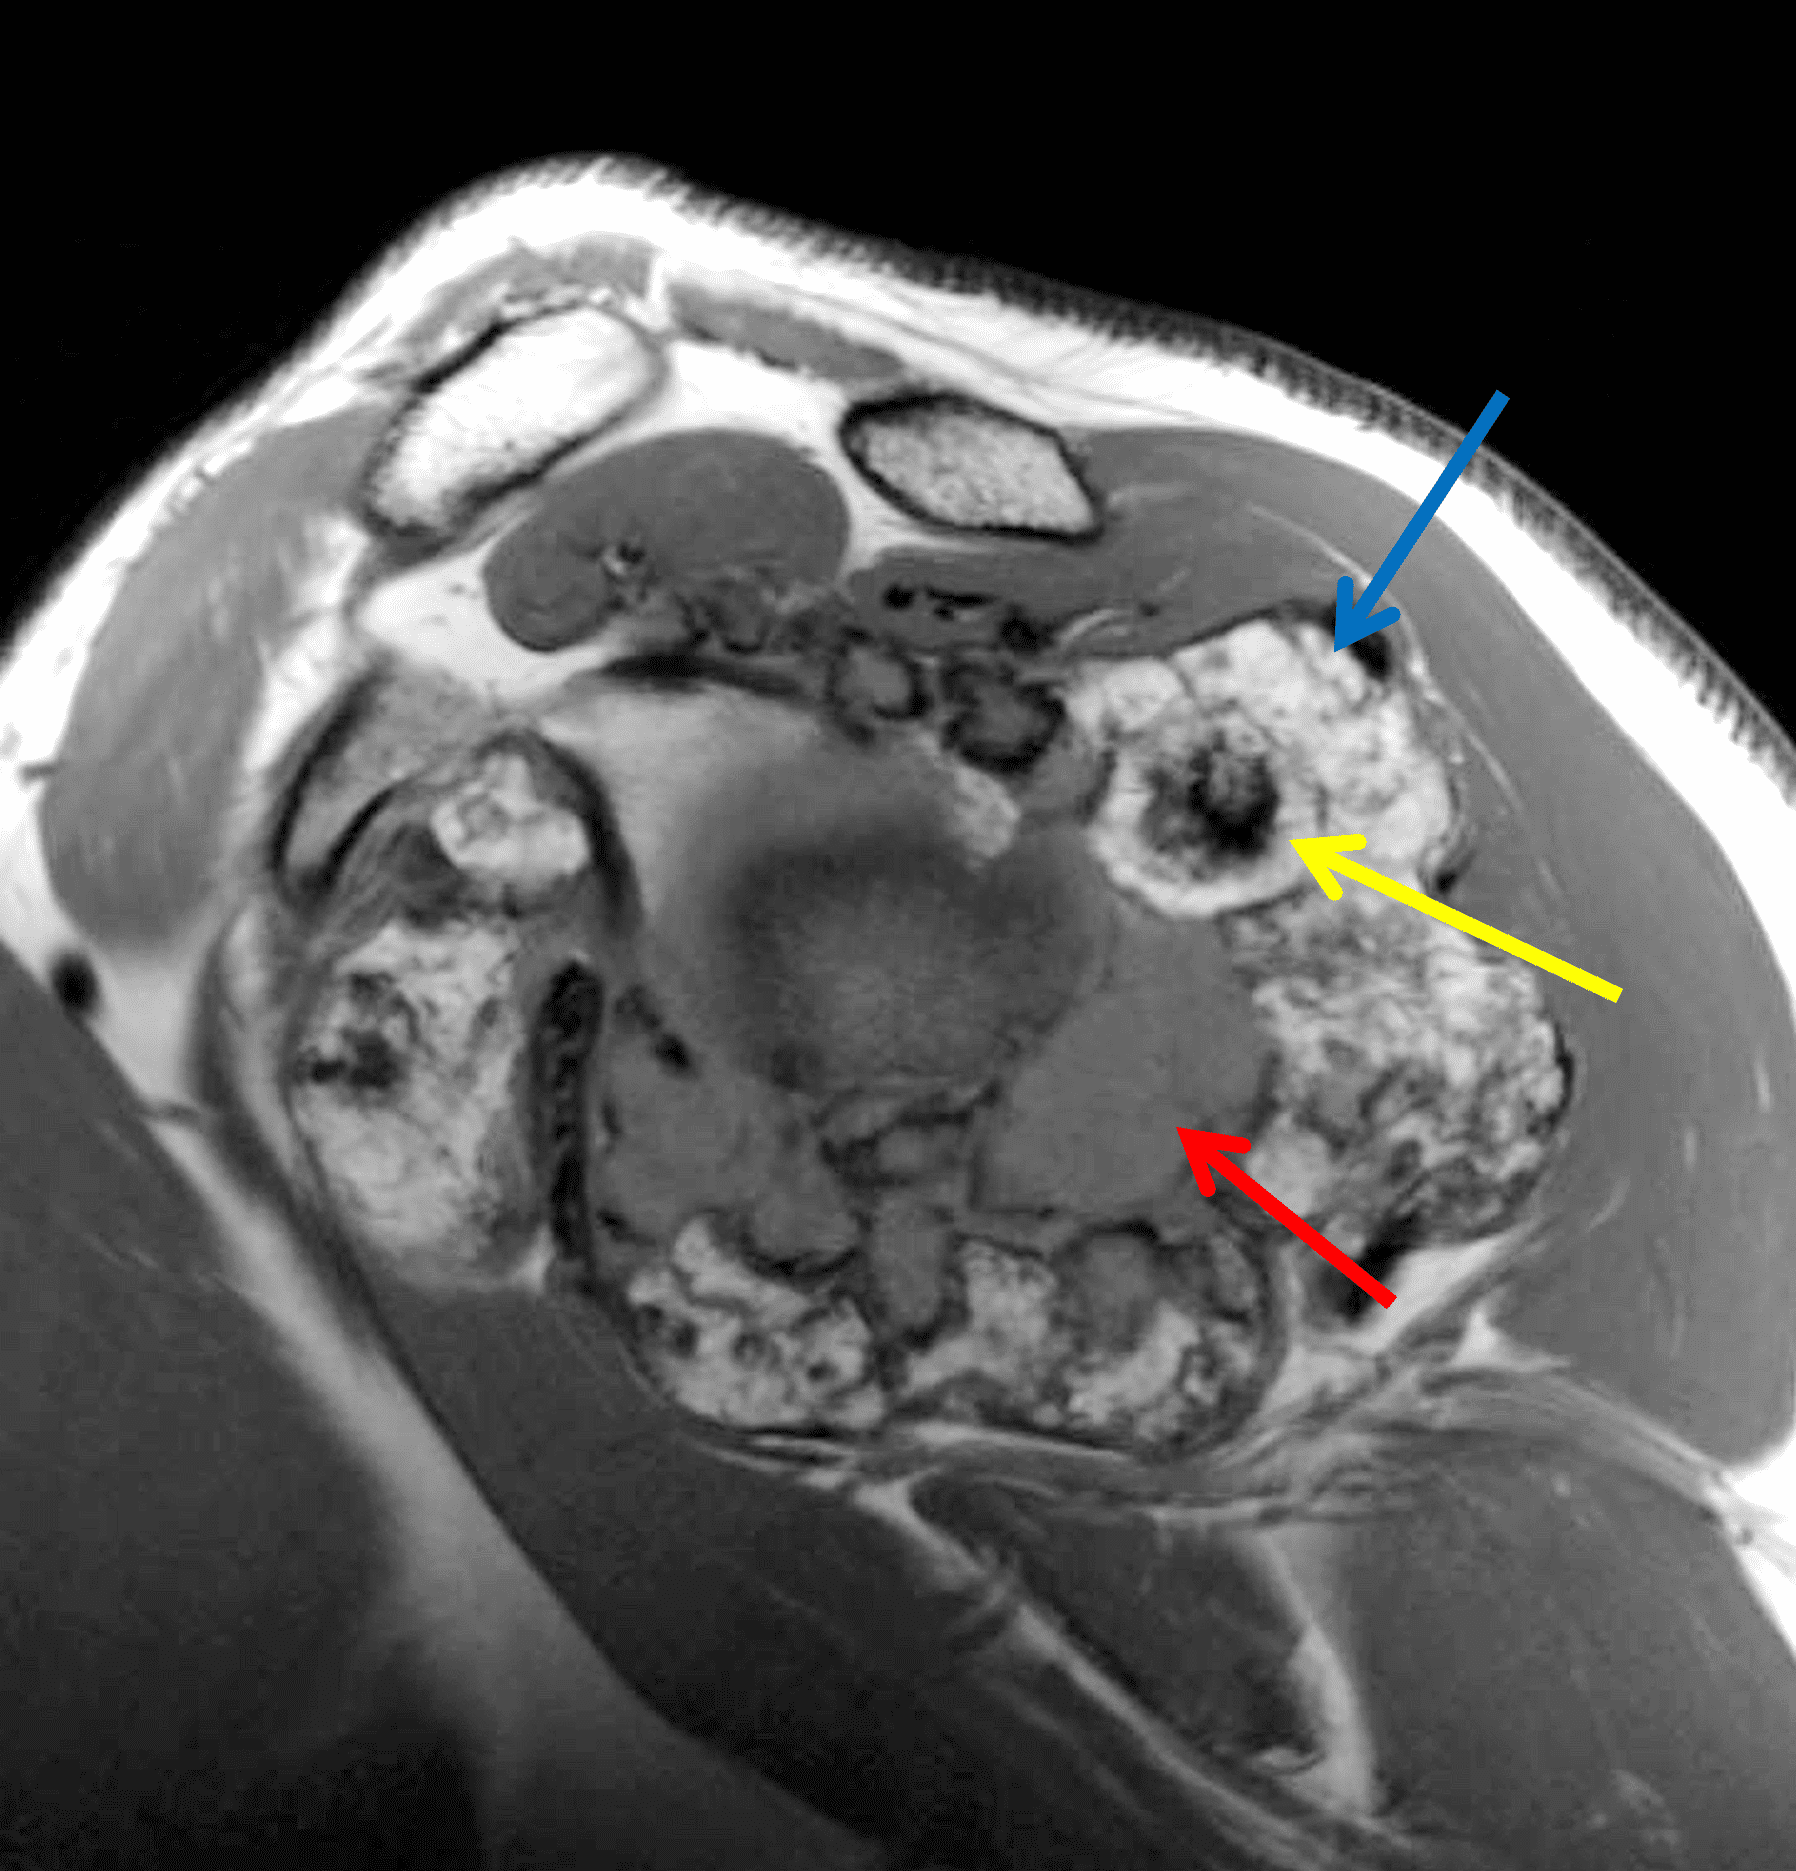

Figure 4: Secondary osteochondromatosis (loose bodies) in the shoulder joint. An axial fat-suppressed T2-weighted image shows multiple intra-articular bodies of variable size (red arrows) and severe glenohumeral cartilage (yellow arrows) due to osteoarthrosis.

Figure 6: Primary synovial chondromatosis in the shoulder joint. Fat-suppressed fluid-sensitive (6A) axial and (6B) sagittal images, and (6C) sagittal T1-weighted image demonstrate diffuse, lobulated synovially-based heterogeneous masses. T2 hyperintense and intermediate T1 signal areas reflect chondroid matrix (red arrows). T1 and T2 hypointense foci reflect calcification (yellow arrows). T2 hypointense and T1 hyperintense foci reflect areas of endochondral ossification (blue arrows). (6D) Axial CT image shows calcification and ossification in the synovial masses, as well as osseous erosions (arrows).